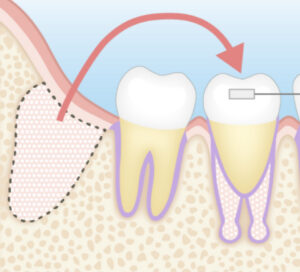

即時インプラント(最新のルートメンブレンテクニック)